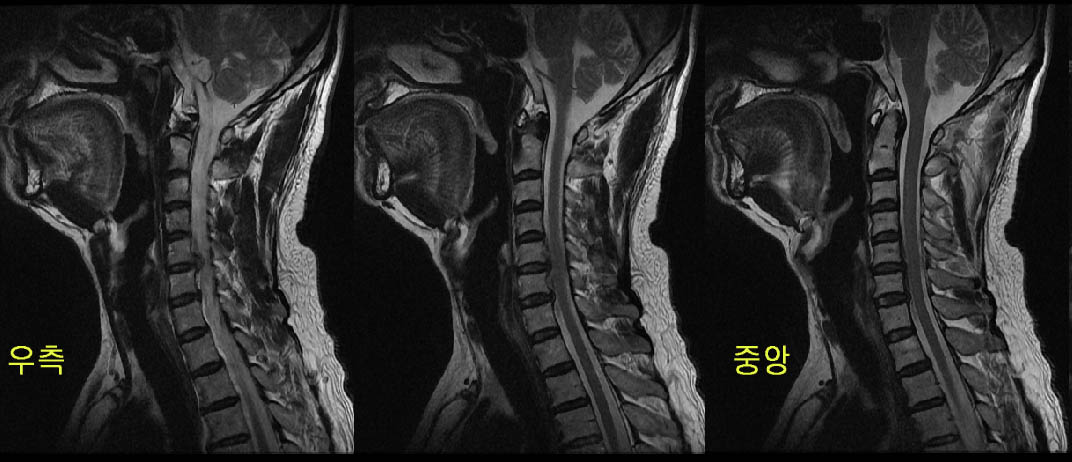

4524 ũ ȸ Ա ġ ۼ 豤* Ȩ/α ۼ 2009-12-29 10:00:20 ̸ kwang2321@yahoo.co.kr 114.53.80.254 ȸ 483 10 ʹ ܰ ġḦ ٸ ȣ̾ 11 MRI˻縦 Ѱ 45 ũ ٰ Ƽ 쿬 ͳݿ ǥغԸ ˰ԵǾ ϱ⺸ٴ ȣɰ ϰ Ǿ Ʋ Ե ȸ ð ģ ħ 3ϸ ȭ Ǿ Ư ȸ MRI ð 4ֵ Ѵٸ ġ ּ̰ ϻȰϰ ֽϴ. 縲 Ƶ͵ ؼ ð ֽϴ. ް Ŵٸ ϰ ѹ ؼ ȸ 帳ϴ. Ȩ,,,,, : ı մϴ 12/29 20091216165803seungeun] 豤 ֹ ֹϽ : 2009-12-16 2009-12-29 15:06:51 Ȩ : 70946-266-96593 ------------------------------------------------------------------------------------------------------------------------------------------------------------------ ڸǥغ ǥغ ȣϽ : Ű : 173 :73 : 47 ˰Ե : ͳ ˻ڷ õ ش : 6C. κ 6C.ھ Ḳ 6C.ڻ ()ũ( ߰Ż) ڸǥغ ġǥغ Ը : ũ(߰Ż), ũ(߰Ż)ġ, , Ḳ , , Ḳ ġ Ǵ ġ ʰ, װ Ǵ ġ ϰ Ѱ : ũ ũ ڰ մϴ, mri Ϸ ڽϴ |